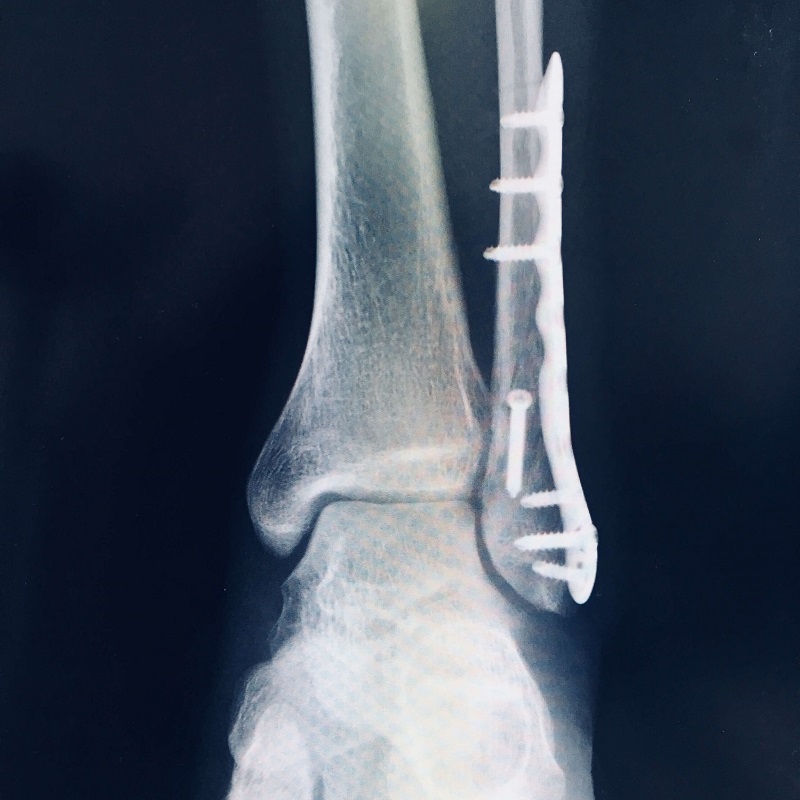

ギブスの代わりに金属プレートを埋め込んだのです。

それがこちらです。

なんと、2×4工法で使う構造用金物みたいなものが

足に入っているではありませんか。

手術後は何があったかはわかっていませんでしたが、

このX線を見て、なんだか痛みを感じるような気がします。